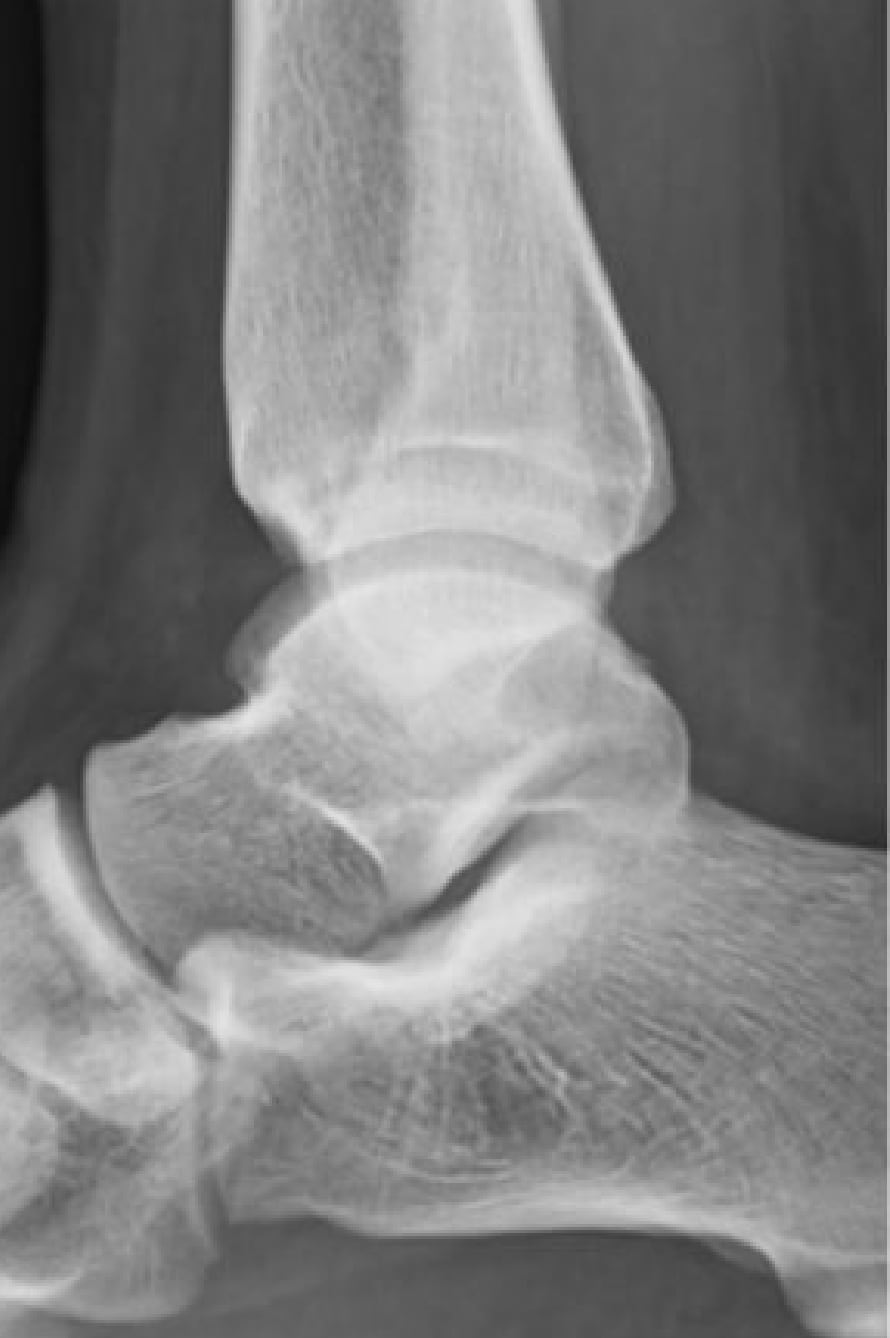

2020-12-09 スポーツ整形 ページ内リンク 後方インピンジメント症候群(三角骨障害)【スポーツ整形外科】 後方インピンジメント症候群(三角骨障害)【スポーツ整形外科】 サッカーやラグビーのキック動作やクラシックバレエのポアント肢位で足関節後方の骨が衝突して疼痛が発生する。⇒鏡視下切除により症状消失。 術前 術後 杉本 武 副院長/スポーツ整形外科センター長 整形外科スポーツ整形 詳しく見る 関連ページ スポーツ整形 一覧へ戻る